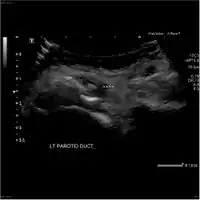

Acute left parotid sialadenitis